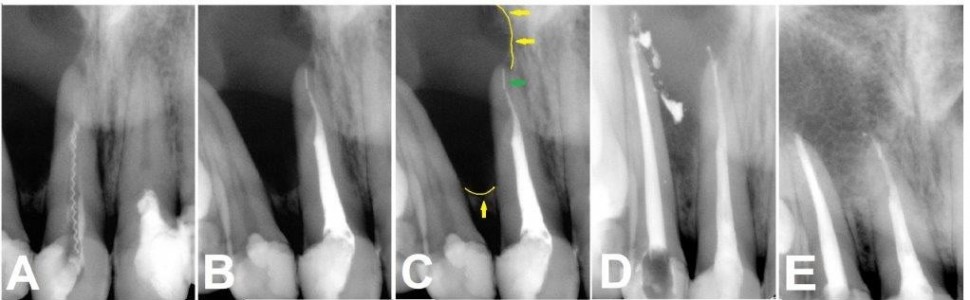

W pracy opisano leczenie endodontyczne zębów siecznych szczęki z rozległą zapalną zmianą okołokorzeniową. W celu odkażenia kanałów korzeniowych zastosowano pastę przygotowaną ex tempore, zawierającą wodorotlenek wapnia i jodoform, oraz dezynfekcję aktywowaną światłem. Zmiana uległa wygojeniu.

The study describes endodontic treatment of maxillary incisors with extensive periradicular inflammatory lesion. In order to disinfect the root canals, a paste prepared ex tempore containing calcium hydroxide and iodoform, and photo-activated disinfection were used. The lesion has healed.